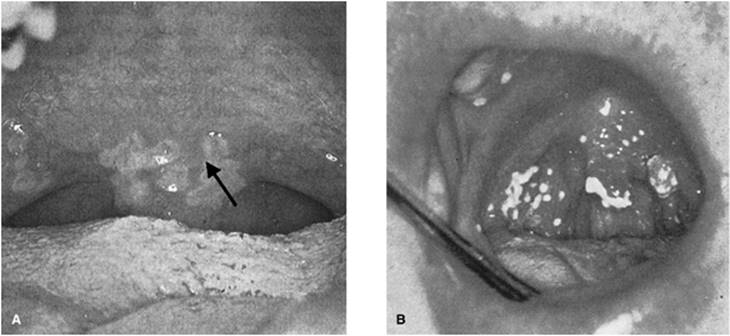

Candidiasis

Candidiasis is caused by overgrowth of Candida albicans. Often the patient is predisposed, with a history of immunosuppression, radiation, or altered microflora following long-term broad-spectrum antibiotic use. In the pseudomembranous form, yellow-white plaques are present that have been likened to milk curds (Fig. 109.6A), whereas in the erythematous form, these plaques have disappeared (Fig. 109.6B). Clinical diagnosis may be confirmed with potassium hydroxide staining revealing fungal hyphae. Initial therapy usually consists of oral hygiene and topical treatment. Some of the available agents include oral nystatin preparations, amphotericin lozenges, and clotrimazole troches. Ketoconazole, fluconazole, and itraconazole can be used for systemic treatment if indicated (63).

Figure 109.6. Oropharyngeal infection by Candida albicans (thrush). These photos demonstrate the pseudomembranous form (A) associated with yellow-white plaques, and the erythematous form (B). (From Walner DL, Shott SR. Infectious and inflammatory disorders. In: Seiden AM, Tami TA, Pensak ML, et al., eds. Otolaryngology: The Essentials. New York, NY: Thieme Medical Publishers; 2001:188, with permission.)